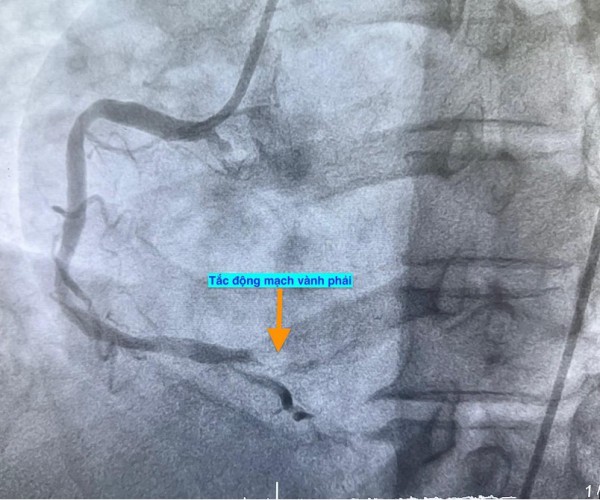

Trường hợp thứ ba, lúc 15 giờ 53 phút, nam bệnh nhân 78 tuổi nhập viện vì đau ngực. Bệnh nhân cho biết đau ngực từng cơn trong 3 ngày, ngày nhập viện thì đau ngực liên tục. Điện tim gợi ý nhồi máu cơ tim cấp; chụp mạch vành cấp cứu phát hiện bệnh nhân cũng tắc động mạch vành phải.

Hình ảnh chụp mạch vành cho thấy các bệnh nhân bị tắc mạch máu tim (do mảng xơ vữa, huyết khối) dẫn đến tình trạng thiếu máu cục bộ và nhồi máu cơ tim cấp

ẢNH: BV